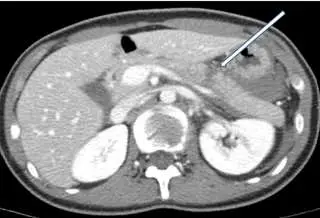

中年男性車禍傷患主訴上腹部劇痛,血壓呈現穩定狀態。電腦斷層檢查如附圖。箭頭所指之異常最可能是下列那一項 初診斷?

本題附圖為腹部軸切面 CT 影像(增強掃描)。影像中可辨識以下結構:中央偏後方為脊椎,兩側為腎臟(呈明顯增強的豆狀構造),左側為脾臟(影像左上方),右側可見肝臟(影像右側低密度組織)。白色箭頭指向影像左側中央區域,對應解剖位置為胰臟體部/尾部(pancreatic body/tail)。

箭頭所指處可見:

- 胰臟實質內出現低密度不均勻區域,提示胰臟撕裂傷(laceration)或挫傷(contusion)

- 胰臟周圍(peripancreatic)有液體積聚,呈現低密度影,延伸至胰臟後方的腹膜後腔(retroperitoneal space)

- 周圍脂肪組織密度增高(fat stranding),提示局部炎症或出血

此 CT 表現符合胰臟撕裂傷的典型直接與間接徵象。腹部鈍傷後的中線附近上腹部劇痛,加上此影像發現,最可能的診斷為胰臟撕裂傷。